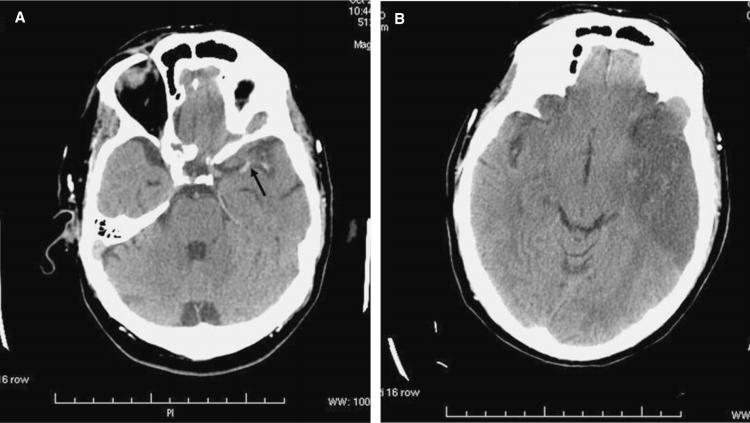

“El ataque cerebral designa a una enfermedad de la cual se altera súbitamente el flujo de sangre en el cerebro. Hay dos tipos principales de ACV: los infartos cerebrales (isquemia), dónde el problema es que el ‘caño se tapa’, y parte del tejido cerebral queda sin su aporte sanguíneo porque un coágulo tapona el vaso. O bien las hemorragias cerebrales, donde ‘el caño se rompe’ y el contenido, o sea la sangre, inunda el tejido”, explicó el médico neurólogo Javier Moschini a ‘Río Negro’.

El 80% de los episodios de ACV son infartos. El 20% restante corresponde a casos de hemorragias.

“Los infartos cerebrales no son dolorosos. Esa es una gran diferencia con el infarto de corazón. En cambio, durante las hemorragias cerebrales, el paciente sufre de manera repentina de un intenso dolor de cabeza, que suele acompañarse de la depresión de la conciencia, y tendencia al sueño”, indicó el médico.